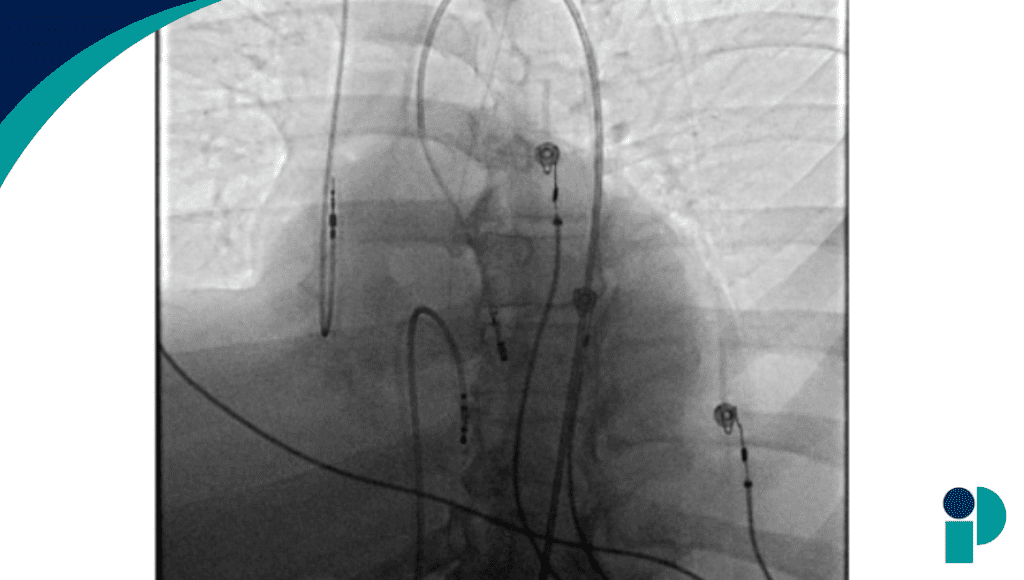

Ante la sospecha de obstrucción biliar, se realizó una colangiopancreatografía retrógrada endoscópica (CPRE) con colocación de stent biliar, lo que produjo inicialmente mejoría clínica y bioquímica. Sin embargo, la verdadera causa de la estenosis no se diagnosticó hasta que el análisis histopatológico reveló trastorno linfoproliferativo postrasplante (PTLD) afectando directamente las vías biliares.